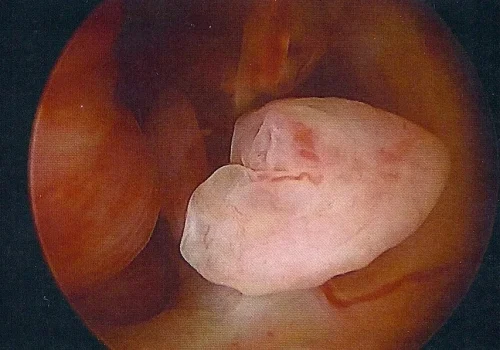

Hysteroscopy – Polypectomy

Procedure

A Hysteroscopy revealed 3 large endometrial polyps which were removed.